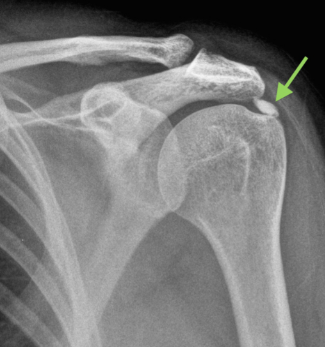

이는 운동 이외 에도 가사노동이나 직업적으로 어깨를 과하게 많이 반복적으로 사용하면서 어깨 질병을 초래할 가능성이 높아지기 때문입니다. 수많은 어깨질병 중에서도 어깨힘줄에 돌이 생기는 석회성건염은 매우 극심한 어깨통증을 일으키는 질병입니다. 어깨 석회성건염은 어깨를 감싸는 힘줄과 연부 조직에 생긴 석회가 끼이는 질병 입니다. 이렇게 힘줄사이에 끼인 석회는 주변을 자극하고 염증을 유발하고 심한 어깨통증을 만들어 냅니다. 어깨를 둘러 싸고 있는 힘줄인 회전근개에 퇴행변화나 혈류 장애로 인해 칼슘 성분이 쌓일 경우 석회성물질로 변하며 이것을 '석회'라 불리게 됩니다.

어깨 석회성건염은 평소에는 어깨통증이 없다가도 갑작스럽게 심한 통증이 생기는 것이 특징이며 주로 나타나는 증상은 어깨에 불이 난것 같은 느낌이 들고 잠을 잘때 자세를 바꿔 아픈 어깨쪽으로 돌아 누우면 심한 통증이 느껴지게 됩니다. 또한 어깨를 만지지도 못할 정도로 아프며 팔을 전혀 움직이지 않았음에도 불구 하고 어깨통증이 있고 어깨 부터 시작 해서 팔과 목으로 통증이 이어 지는 느낌도 있으며 밤에 통증이 더 심해지는 것등의 증상이 있습니다. 이중 3가지 이상의 증상이 있다면 어깨 석회성건염을 의심 해야 합니다.